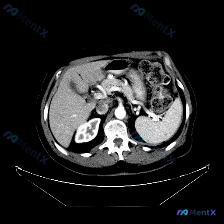

这是一份腹部CT横断面的分析:

- 实质脏器:肝、胰、脾、肾都大致正常——肝脏密度均匀,胰周脂肪间隙清晰,脾脏形态/大小正常、密度均匀无占位,双肾皮髓质分界可、无积水;

- 血管与淋巴结:腹主动脉壁见少量斑片状高密度影(提示血管粥样硬化钙化),门静脉、下腔静脉走行正常,腹腔干及腹主动脉周围未见明显肿大淋巴结;

- 其他:无腹腔积液、无占位效应、无脂肪间隙浑浊,胃壁也未见明确增厚。